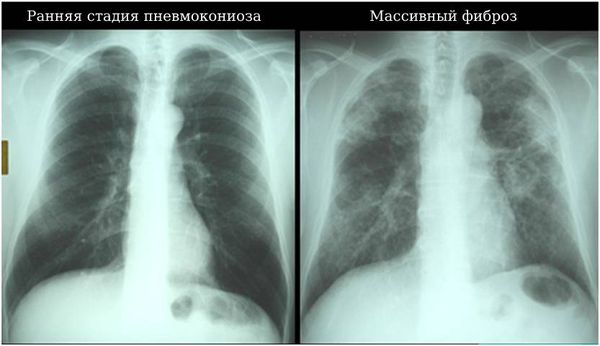

Рентгенография грудной клетки в двух проекциях, полипозиционная рентгенография, первично увеличенная рентгенография, линейная томография. При подозрении на пневмокониоз рентгенография выполняется в первую очередь, так как позволяет определить стадию болезни и тактику лечения.

![Ранняя стадия пневмокониоза и массивный фиброз лёгких [15] Ранняя стадия пневмокониоза и массивный фиброз лёгких [15]](/media/bolezny/pnevmokonioz/rannyaya-stadiya-pnevmokonioza-i-massivnyy-fibroz-lyogkih-15_s.jpeg)

Ранняя стадия пневмокониоза и массивный фиброз лёгких [15]

Международная организация труда выделяет три стадии болезни, основанные на рентгенологических изменениях:

- I стадия (мелкоузелковая) — просовидные тени в верхушках лёгких.

- II стадия (интерстициальная) — слияние узелков в более крупные формы с последующим уплотнением.

- III стадия (узловая) — увеличение образований более 1 см, наличие буллёзной эмфиземы, спаек между плеврой и диафрагмой или плеврой и перикардом. Часто эта форма возникает после прекращения контакта с кварцевой пылью, это так называемый «поздний силикоз». Внутри крупного узла может образоваться каверна (полостное образование), что резко отягощает течение болезни и нередко приводит к летальному исходу.